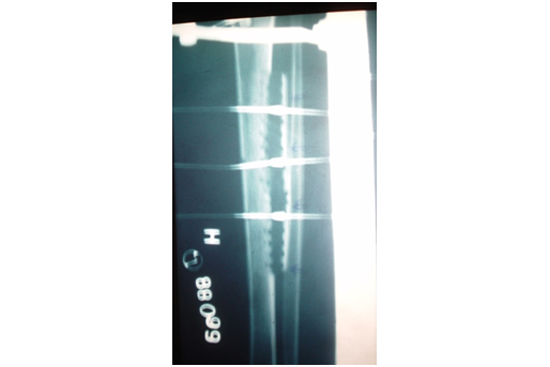

1. Frame fixation done for lateral distraction of spitted tibia.(FIG 3)

2. Distraction at a rate of .25 mm / 6 hourly means 1 mm per day was continued for 20 days. So wound became cherry red with healthy granulation tissue and development of micro circulation.